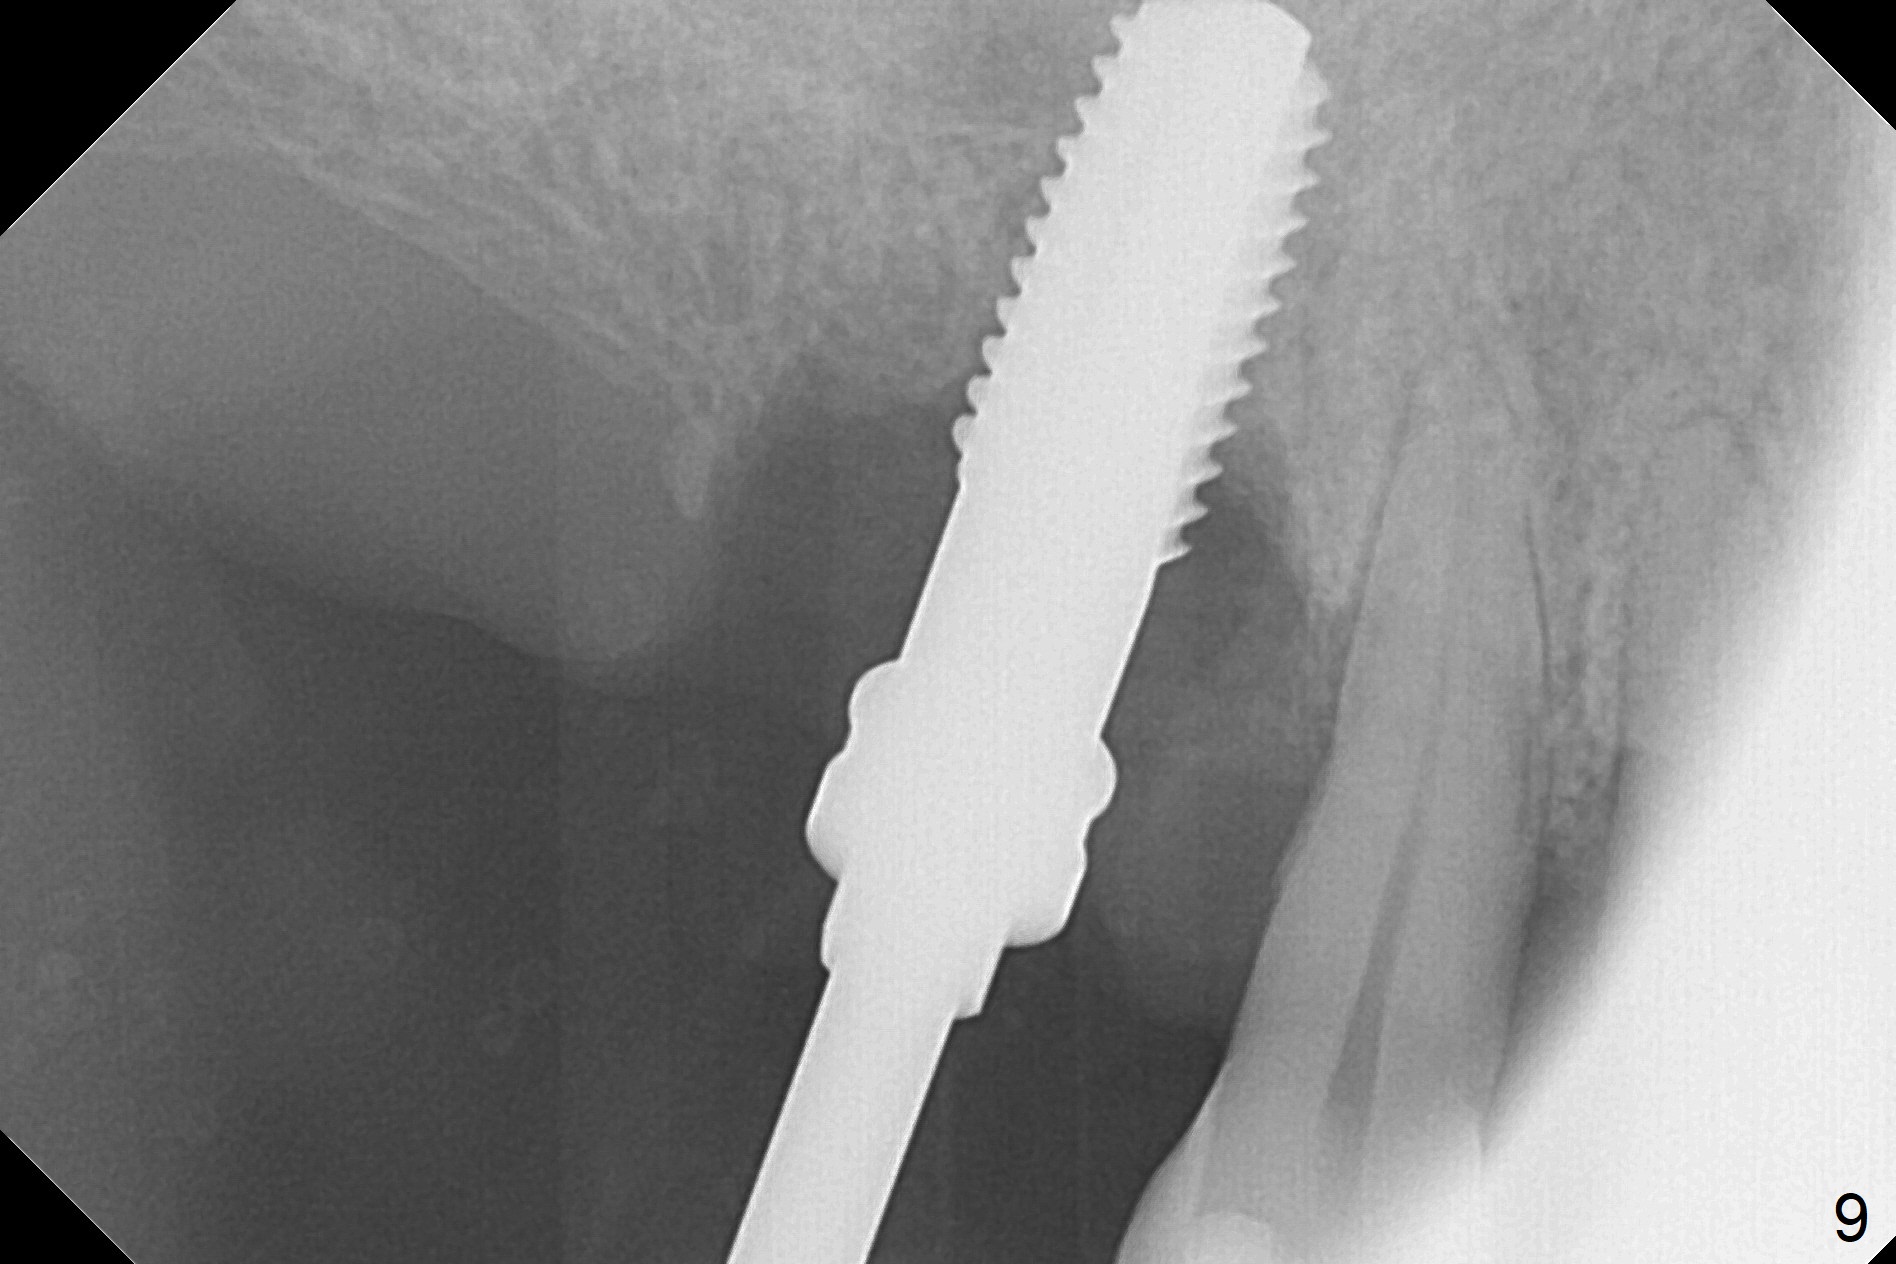

After extraction of the tooth #3 (Fig.1,2), the palatal socket (P) is as wide as the buccal one (B; Fig.3,4 (socket impression)), as compared to the roots), suggesting bone loss is more severe palatally than buccally. There is a circular area in the buccal slope of the palatal socket, in which the bone looks thin (purplish: presumably the sinus membrane underneath, Fig.5,7 (blue circle)). It appears that the palatal slope of the buccal socket (Fig.6, 7 red dashed line) is the most appropriate site for osteotomy (Fig.8). Prior to inserting 5.3 mm tap drill (Fig.9), the mesiopalatal region of the osteotomy (corresponding to the blue circle in Fig.7) perforates without sinus membrane tear. A small piece of Osteogen plug is placed in the perforation before inserting a 5.3x10 mm SM implant (Fig.10,11). Following placement of another piece of Osteogen plug in the palatal socket and of a 4.8x7(6) mm abutment, mineralized cortical and cancellous bone is placed (*). Collagen plug and an immediate provisional are used to close the socket opening. CT taken 11 months post cementation shows that the implant is placed within bony boundary, although buccally (Fig.12 B). Bone graft seems to heal in the sinus (Fig.13 (sagittal section),14 (coronal section) white * (Osteogen plug) and in the socket (brown * (allograft and Osteogen)).